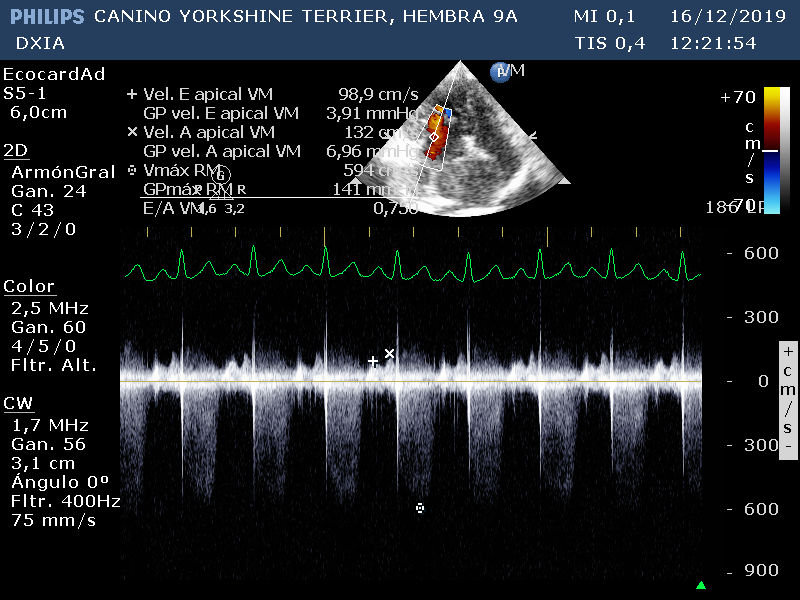

Corte apical izquierdo 4 cámras doppler continuo en VM. Valva septal engrosada presentando nodulaciones. Valvas no coaptan correctamente. Flujo regurgitante con GP severo.